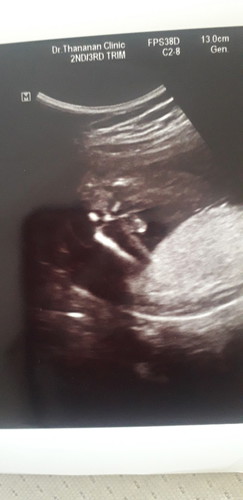

ซาวตอน 16 w หมอบอกผู้ชาย เพิ่งซาวมาเมื่อวานค่ะ นางไม่ให้ความร่วมมือนางนอนคว่ำหน้าค่ะเลยไม่เห็นอะไร แต่หมอซาวช่วงหว่างขาเห็นปิ๊กกาจู๋ หมอบอก ผู้ชาย เป็นไปได้ไหมค่ะ จะคลาดเคลื่อนเพศ อยากซื้อของให้ลูกแล้วคะ ?

ผู้ชายโอกาสพลาดน้อยกว่าค่ะ ถ้าเห็นจุ๊ดจู๋ แต่มีบางเคส สายสะดืออยู่หว่างขาก็มีค่ะ เลยคิดว่าเป็นผู้ชาย แต่เป็นไปได้ยาก

ผู้ชายเหมือนกันค่ะ 17วีค หมอบอกมีจู๋แต่เราดูไม่เป็น

อันนี้ก็ท่าไหนไม่รู้ค่ะ แต่หมอบอกผู้ชาย

แบบนี้ชายชัวร์มั้ยคะแม่ๆ

แบบนี้หมอก็บอกผู้ชายค่ะ